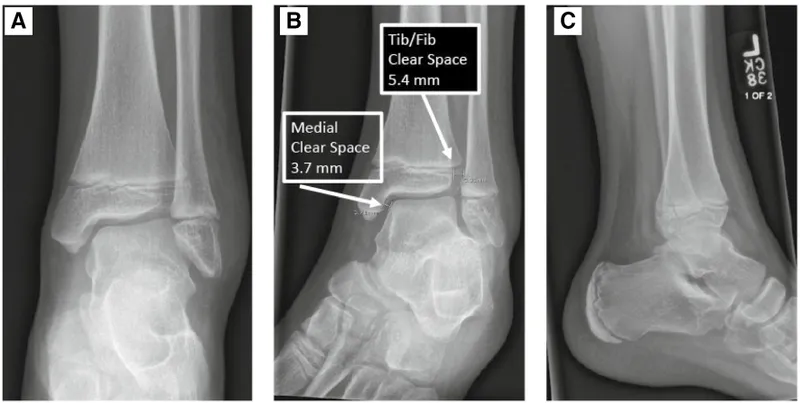

- Ankle Joint Alignment

- Mortise: Joint space should be uniform. Widening suggests ligamentous injury.

- Tibiofibular Overlap: On AP view, should be >6 mm. Less overlap suggests syndesmotic injury.

- Increased medial clear space (>4 mm) in the ankle points to a deltoid ligament rupture.